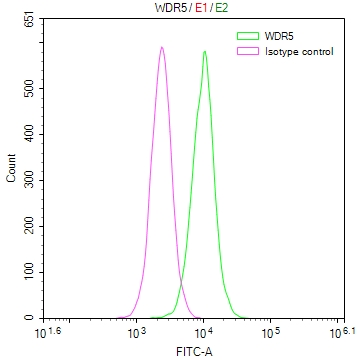

Immunofluorescent analysis of Hela cells using CSB-PA10599A0Rb at dilution of 1:100 and Alexa Fluor 488-congugated AffiniPure Goat Anti-Rabbit IgG(H+L)